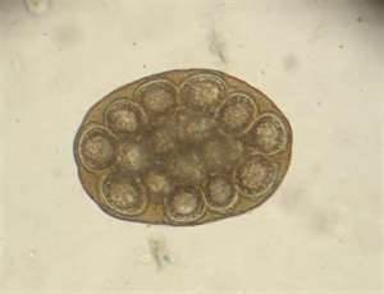

This was found on the fecal of a horse. What is this parasite?

Parascaris equorum